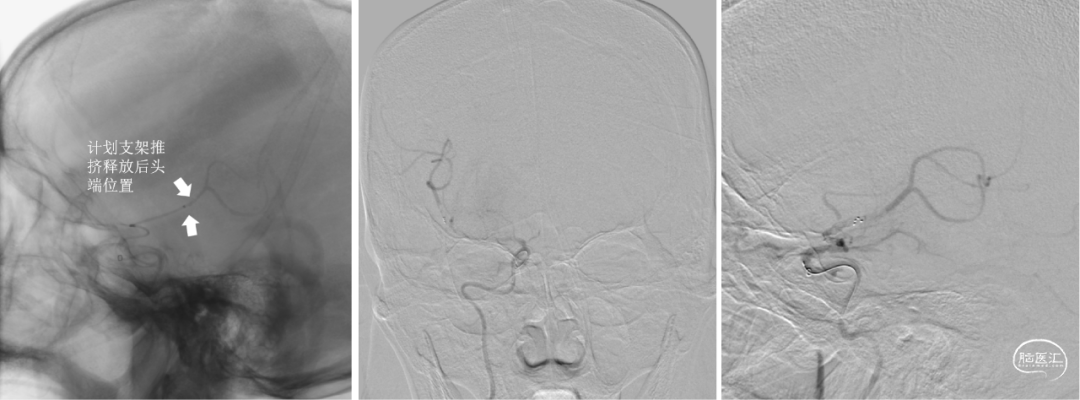

Catalyst 7再次通过闭塞处于C2-C4近端抽吸,再无血栓抽出,球囊辅助通过(BTA)技术无法将CAT7带入C4远端,CAT减容任务完成,使用Solitaire FR 6×30支架行完整BADDASS技术, 6×30支架前行张力非常大,释放时并无法顺利推出Rebar 18微导管,导致支架释放略近于预期位置。

支架释放位置不理想,而且前行过程中导致血栓前移,支架并未覆盖血栓头端,经验告诉我们,仅靠软膜支的独立系统可能会通过BGC的血流阻断弥补前向压力(P),远端未覆盖血栓可能会因为血栓之间的粘附力而一并拖出。

BADDASS技术下支架取出长条血栓,3D-DSA可见眼动脉下方重度狭窄,CAT 7在张力下的上行切割狭窄处,导致小夹层产生。

术后RICA造影 :mTICI 3级。

Reexamination Cranial DWI:无明显的血栓向远端逃逸或小血栓脱落后新形成的皮层或分水岭点片状梗死。

Reexamination Cranial SWI:壳核后部,造影剂渗出最多的地方再灌注损伤。